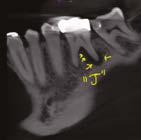

A 48-year-old female patient presented to the graduate endodontic clinic with a referral to evaluate and treat tooth No. 11 through the existing crown. The patient’s chief complaint was, “I was told a year ago I had an infection, but it hasn’t bothered me. They told me I needed a root canal to get rid of the infection.” The patient had no significant health history or any known drug allergies. Dental history for tooth No.11 included multiple restorations followed by a final core and crown in 2019. The adjacent tooth, No. 12, was replaced with an implant in 2018 and restored in 2019, 6 months following final crown of tooth No. 11. Upon examination of records, a periapical radiolucency on tooth No. 11 was visible on the day of crown fabrication and delivery (Figure 1). There was no note of this lesion in the patient’s record. An updated radiograph was taken during a periodic oral exam in September of 2023 showing clear delineation of the periapical radiolucency on tooth No.11 (Figure 2).

Figure 1 (left): Periapical radiograph taken at the time of tooth No. 11 crown delivery in 2018 with a periapical radiolucency extending distally toward implant No. 12. Figure 2 (right): Updated periapical radiograph taken in 2023 during a periodic oral exam showing clear delineation of a periapical radiolucency associated with tooth No. 11